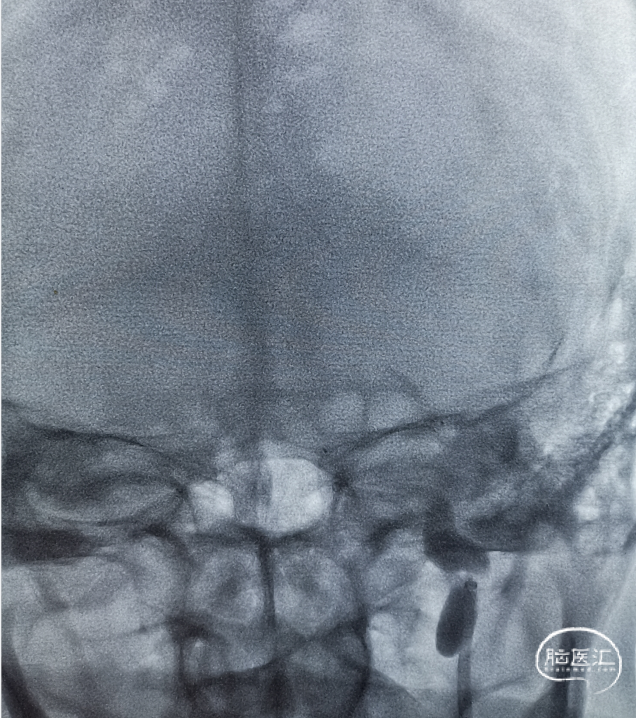

查血常规、生化、凝血未见异常;心电图提示心房纤颤;头颅CT示多发性脑梗死,左侧大脑中动脉高密度征;头颅CTA提示左侧颈内动脉末端闭塞。拒绝静脉溶栓治疗,转至我院行急诊机械取栓。

头颅CT

头颈部CTA